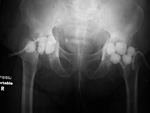

Bilateral hip antibiotic beads in a patient with infected hips after girdlestone procedures

Pelvis radiograph. There are bilateral surgical drains and a catheter with a distended balloon in the bladder.